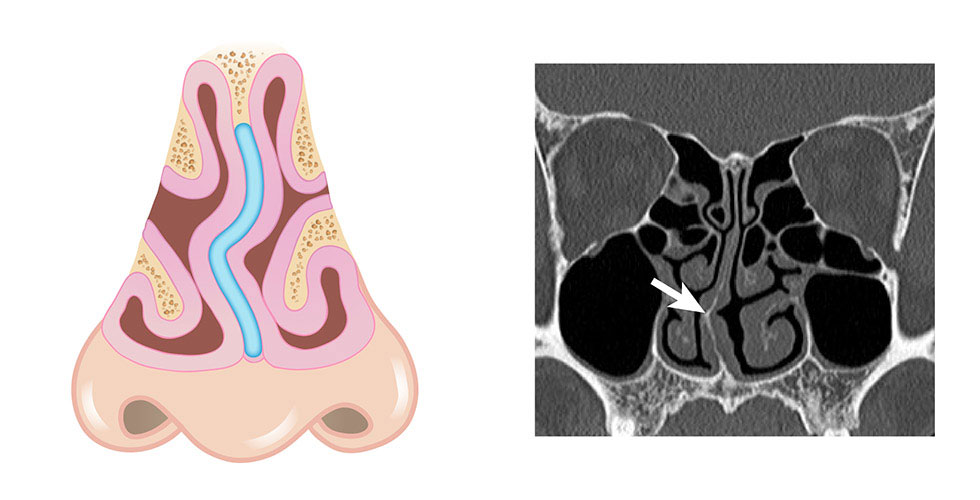

鼻中隔是由軟骨及硬骨所組成的一道隔板,將鼻腔分成左右兩側。原則上,它應該位於鼻腔正中央,但在成長過程中,可能因為外力影響,導致兩側生長不均,進而使鼻中隔逐漸彎曲。事實上,大部分的鼻中隔都有輕微偏曲,但並非人人都會出現明顯症狀,外觀未必有異常。

當鼻中隔彎曲嚴重,或是合併下鼻甲肥厚時,可能會引發鼻塞,影響正常呼吸。有些人因先天或外傷造成外觀變形,導致鼻中隔彎曲更加嚴重。此狀況會改變鼻腔氣流,使呼吸受阻,進而影響睡眠、專注力及整體生活品質。若藥物治療無效,通常需藉由手術來有效改善鼻塞問題。

此外,鼻中隔彎曲常合併肥厚性鼻炎,使鼻道空間狹小,近一步影響氣流,導致鼻塞加劇。

▲ 鼻中隔彎曲常合併肥厚性鼻炎,造成主鼻道空間狹小,影響氣流因而有鼻塞的現象產生。